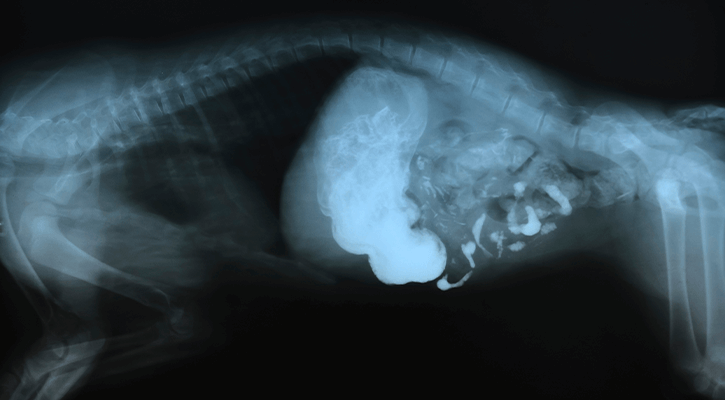

X-rays, or radiographs, utilize electromagnetic radiation directed toward the body to produce images that highlight internal structures. These images are invaluable for detecting various abnormalities, including skeletal fractures, soft tissue damage, foreign bodies, and dental disease.